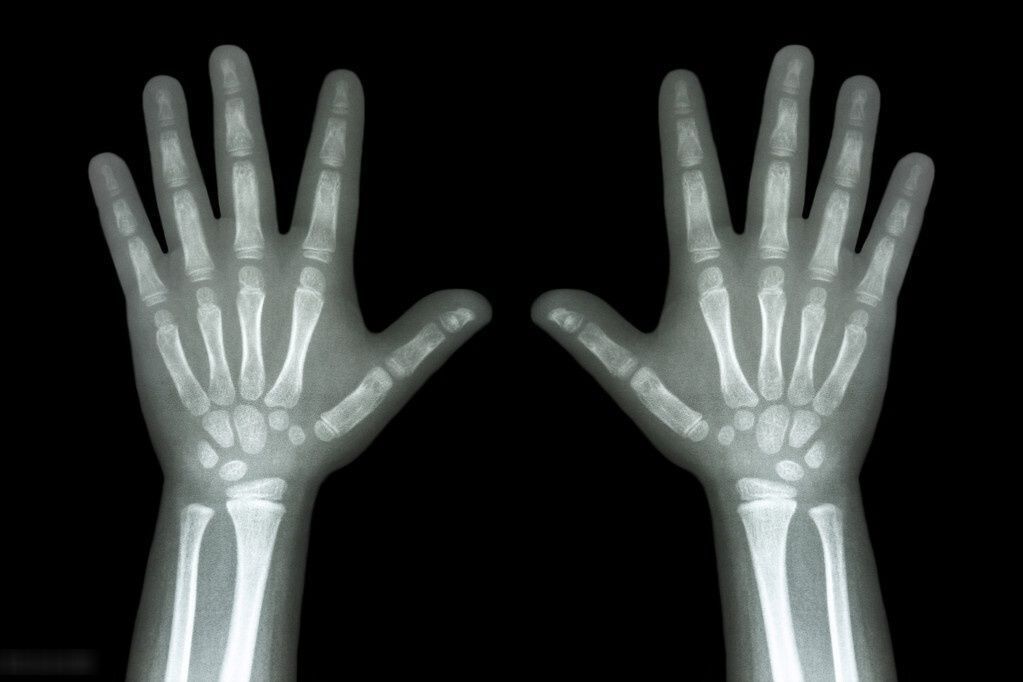

有一种说法是:“孩子个子的高矮与骨龄有关。”

去医院检查,医生也会让家长带孩子“拍骨龄”,很多家长往往困惑不解:骨龄是什么?为什么要查骨龄?

骨龄过大过小都可能影响身高。当家长发现孩子身高矮于同龄人时,应及时带孩子检查,孩子的长高空间还有多少并不能仅从一次骨龄进行判断,需要长期追踪和观察孩子的生长发育情况,观察骨龄进展的快慢,找出影响孩子长个的因素。只是依靠单纯的拍骨龄,无法保证孩子的生长发育和身高需求。